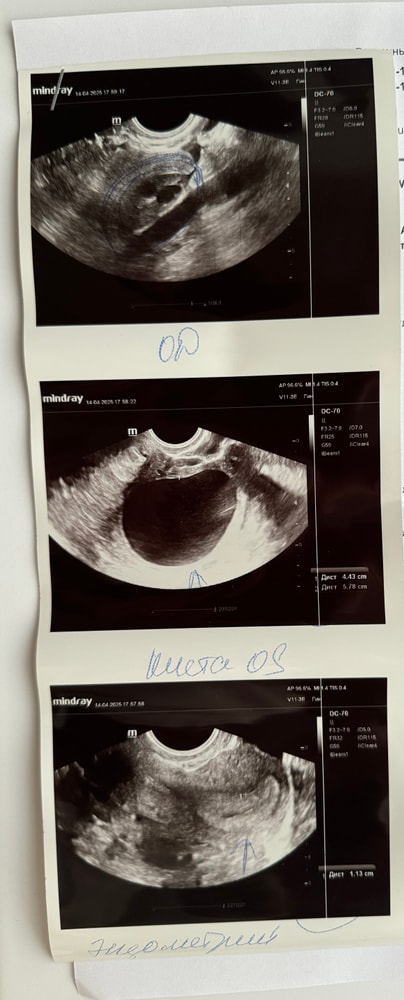

была на узи, результаты неутешительны🫤 поймала тестами овуляцию, но были очень сильные боли, решила сходить на узи, подтвердить овуляцию и заодно посмотреть, что там да как.

доктор сказала киста 6 см🥲 но при этом сказала, что все супер у меня. Я начала задавать вопросы, так как не поняла вообще, получается желтого тела нет. Сказала пусть вам доктор все объясняет🫠 в конце сказала, что может быть это желтое тело, говорит они тоже таких размеров могут быть. Получается она не смогла отличить кисту от ЖТ?🤓

На жт не похоже. Скорее фоллик не лопнул.